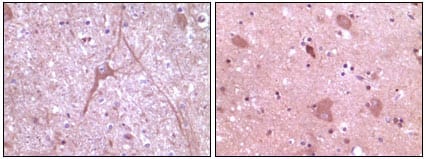

分类: 科研抗体货号: 20105别名: BP-1; 4EBP1; 4E-BP1; PHAS-I; MGC4316; EIF4EBP1应用: IHC反应种属: Human

分类: 科研抗体货号: 20127别名: HER-2, C-erB-2, erbB-2应用: IHC反应种属: Human